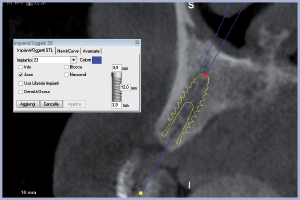

Dopo aver eseguito l’esame, i file dicom vengono acquisiti dal software di programmazione 3Diagnosys LEONE. Studio in modo accurato l’anatomia del mascellare superiore verificando la possibilità di inserimento di impianti nei siti edentuli. Nel quadrante superiore destro progetto in zona 14 e 15 due impianti Exacone® Max Stability 3,75 x 12 mm e nel quadrante superiore sinistro nelle zone 23, 24, 25 e 26 rispettivamente un impianto Exacone® Max Stability 3,75 x 12 mm, un impianto Exacone® 3,3 x 12 mm, un impianto Exacone® Max Stability 3,75 x 10 mm e un impianto Exacone® Max Stability 4,5 x 8 mm (Figg. 1-10).

- Figg. 4-9 – Impianti pianificati visti nelle “cross section” su software 3Diagnosys Leone

- Fig. 5 – Impianto posizione 15